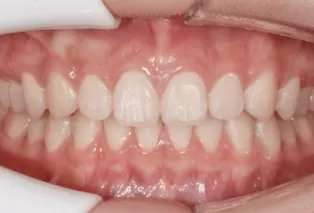

Intraoral photos after treatment